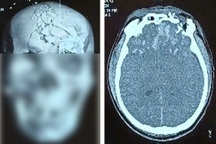

Thiếu niên cùng số pháo nổ tự chế tại cơ quan chức năng (Ảnh: Tú Anh).